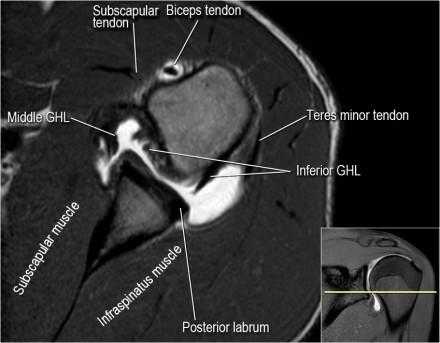

Нормальная анатомия плечевого сустава в аксиальных изображениях и контрольный список.

- обратите внимание на волокна нижней плече-лопаточной связки. На данном уровне так же ищется повреждение Банкарта.

- изучите область прикрепления нижней плече-лопаточной связки. Изучите нижний комплекс суставной губы и связок. Поищите HAGL-повреждение (humeral avulsion of the glenohumeral ligament).